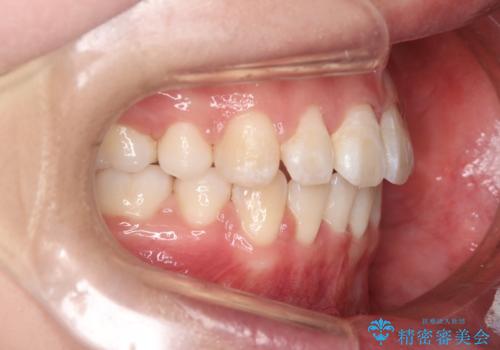

- 前歯のがたつきと口元を気にされて来院されました。

上下4番目の歯を抜歯してがたつきを改善しながら口元を下げる治療計画を立てました。

抜歯矯正をして口元を下げたことで、口元が下がりEラインが大変綺麗になりました。

矯正期間も1年9ヶ月と比較的短期間で終了することができました。